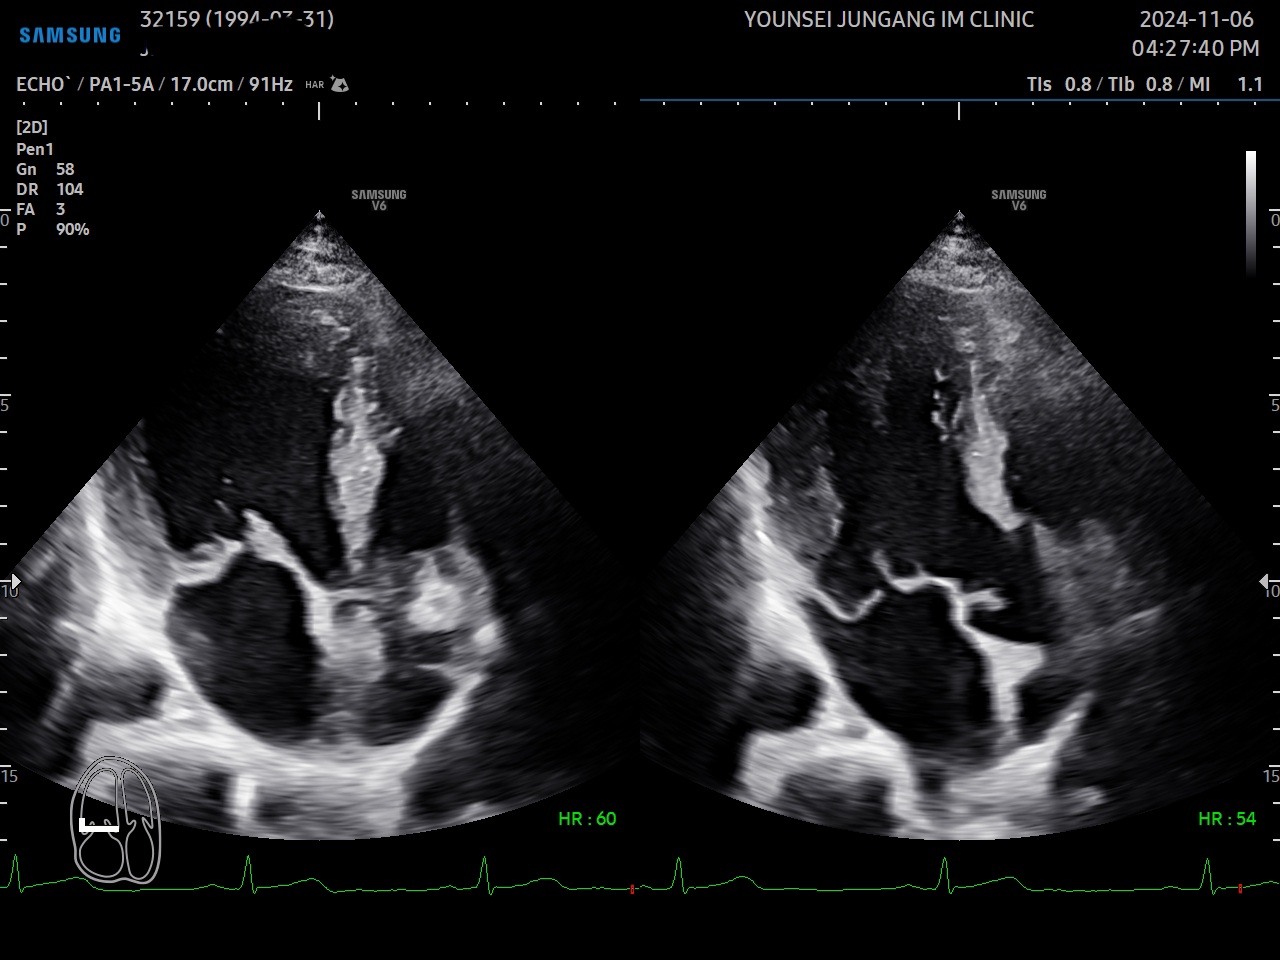

È®À强 ½É...